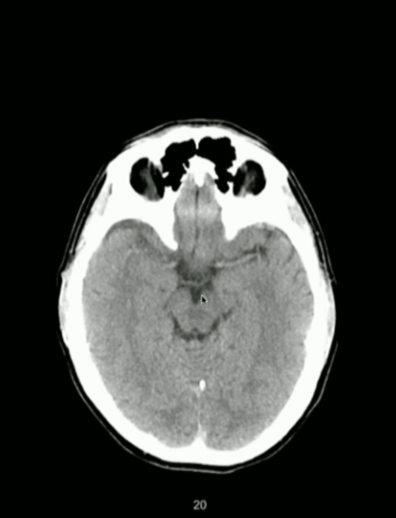

<p>What Part of Brain Stem?</p>

What Part of Brain Stem?

• Pons

• Look for Basilar Groove